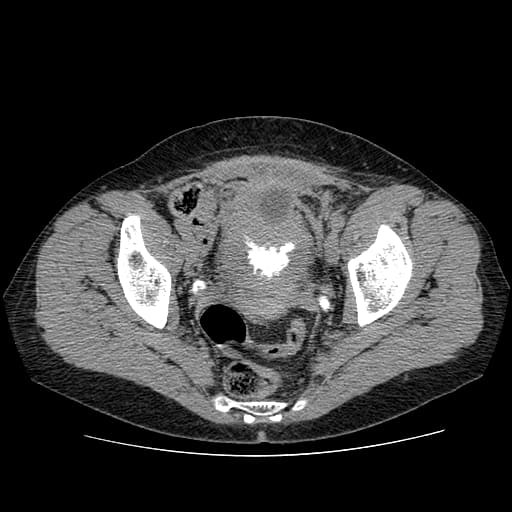

Все о КТ мочевого пузыря

КТ мочевого пузыря в диагностических центрах Санкт-Петербурга активно применяется при исследовании состояния структур мочевыделительной системы и при подозрении на патологические изменения в них. В основу компьютерной томографии заложено использование рентгеновских лучей. Если проводят КТ мочевого пузыря с контрастом, то йодсодержащее вещество дополнительно увеличивает четкость отображения органов на снимках и способствует выявлению опухолевых заболеваний на раннем этапе. Такой метод диагностики признан эффективным и относительно безопасным, так как обследование проводится в течение нескольких минут, и уровень лучевой нагрузки на организм составляет 5-7 мЗв.

Компьютерная томография мочевого пузыря назначается для подтверждения диагноза при отсутствии точной информации от предыдущих исследований (УЗИ или рентгенография) и для текущей оценки функционирования мочевыводящих путей и мочевого пузыря. С помощью современной мультиспиральной КТ можно определить наличие патологий и воспалительных процессов до начала появления у пациента явных симптомов заболевания. По результатам диагностики можно выявить:

Подозрение на опухоли и объемные образования чаще всего предполагает проведение КТ мочевого пузыря с контрастным веществом. Задача контраста заключается в проникновении в ткани и усилении видимости пораженных участков. Исследование с контрастированием способствует обнаружению патологических процессов на ранней стадии развития. МСКТ мочевого пузыря с контрастом позволяет выявить опухоль размером до 1 мм, определить ее масштаб и доброкачественный или злокачественный характер.

МСКТ мочевого пузыря проводится с помощью специального оборудования – мультиспирального компьютерного томографа, который может обладать разными срезовыми возможностями (от 8 до 640 срезов за один оборот сканирования). После расположения обследуемого на выдвижной части томографа ее задвигают в полость КТ аппарата. Совершая обороты вокруг тела обследуемого, сканер передает изображения органов на компьютер, который выводит их в виде трехмерной модели. Время проведения диагностики составляет около 5 минут, а при контрастной процедуре увеличивается до 20 минут. По окончании этапа сканирования начинается расшифровка результатов обследования.

Рентгенолог диагностического центра рассматривает полученные томограммы и делает описание. Специалист проводит детальный анализ размеров органов мочевыделительной системы. В случае обнаружения отклонений он описывает степень повреждения тканей, плотность и стадию развития опухоли, указывает месторасположение и масштаб распространения инвазии или воспалительного процесса.